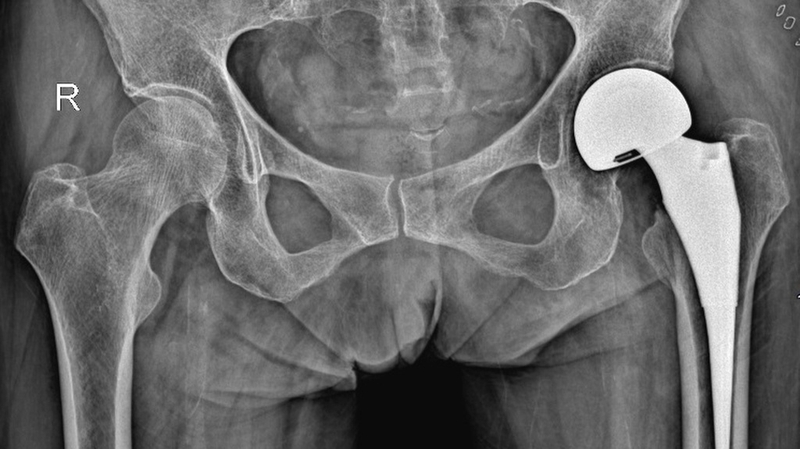

Phẫu thuật thay khớp háng được thực hiện để cắt bỏ khớp háng bị tổn thương và thay thế bằng khớp nhân tạo. Thông thường, phương pháp này chỉ được chỉ định đối với những trường hợp bị tổn thương khớp háng nghiêm trọng và không thể điều trị bảo tồn. Ở Việt Nam, kỹ thuật này đã phát triển được hơn 40 năm và đã có hàng nghìn ca bệnh được thay khớp háng thành công mỗi năm. Giúp người bệnh thoát khỏi đau và khó chịu, tái khôi phục khả năng vận động và mở ra cuộc sống mới.

Phẫu thuật thay khớp vùng háng được xem là một thành tựu to lớn trong lịch sử phát triển ngành chấn thương chỉnh hình. Kỹ thuật y khoa này thường được thực hiện ở những bệnh viện lớn với đội ngũ chuyên gia và thiết bị hiện đại, cho tỷ lệ thành công cao.